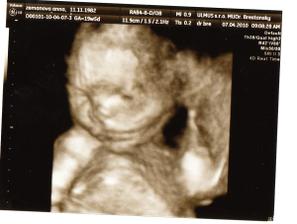

Začali sme sa nanovo snažiť tak uvidíme ako dlho to potrvá dostať sa k cielu.15.12.2009 som dostala taký predčasný vianočný darček // na testíku. 18.12 boli sme u dr ešte nebolo nič vidieť tak maminu pochytila panika ale hcg je 465 takže tehu sme len ešte malíčko a zase sa bojím či je to ok:-// 23 sme boli u dr chytili ma ladviny tak som dostala ant. ale fazulka sa má zatial ok je presne tak kde má byť vačok má 8 mm a už je tam aj základ bábenka.🙂)) Aby ani druhé bábenko nezaostávalo za Kubkom tak mamine je zase poriadne zle už aby bol 12 tt a trochu to prešlo. 14.1 boli sme kontrole všetko ok krásne bilo srdiečko. Dostali sme tehu knižku a prenatal box. 28.1 nás čaká ultrazvuk tak sa už moc teším.Stále my je dosť špatne a už aj vraciam čo už:-/// 2.2. dnes sme boli na utz všetkoje v poriadku aj ked dr najskôr bábo nemohol nájsť po chvílke ho predsa vypátral. všetko je ok bábenko meria 6,68 cm a crl má 4,6 cm. tak na dalšej kontrole sme sa dozvedeli že naše prekvapenie bude chlapček tak budeme mať Mateja- Maťka dalšia poradna za namy všetko ok dalšia nás čaká 7 apríla a konečne znova uvidíme drobčeka. Všetko dopadlo dobre Matejko je trošku večší ale hlavne je ok. 10.5 Gtt hádam budu dobré výsledky inak všetko v norme len bruško je trošku večšie o 2 týždne kontrola tak uvidíme na tvrdnutie sme dostali mange b6 2x dene tak hádam to pomože. Boli sme na sone 17.6 a Matko chce asi predbehnut porodnou váhou Kubka už teraz má 2107 g a aj ostatné rozmery su chválihodné inak je všetko v poriadku pekne si kopká a už sa moc tešíme